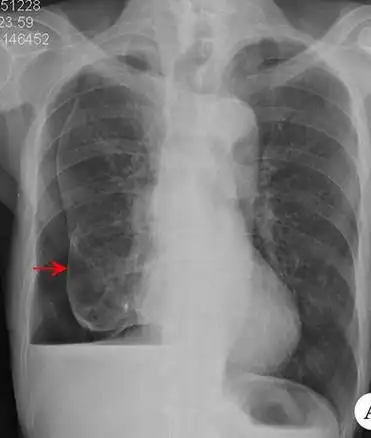

气胸的x线表现,6个病例搞定!

气胸患者胸部x线表现

一侧气胸肺严重压缩

左侧气胸(肺被压缩约20%)